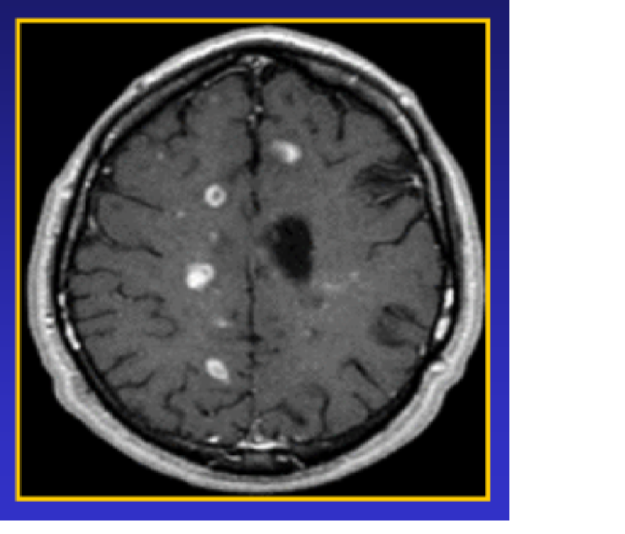

MS (MULTİPL SKLEROZ) nedir? Multipl skleroz, vücudun kendi bağışıklık sisteminin beyindeki, optik sinirdeki ve omurilikteki sinir hücrelerinin koruyucu kılıfına (miyelin kılıfı) karşı yöneldiği bir hastalıktır. Aslında bu kılıf bazen elektrik telindeki yalıtıma benzetilir. Sinir hücreleri sinir tellerini oluşturur bunlar da mesaj iletimini gerçekleştirir. Merkezi sinir sistemi ile organların bilgi iletimi bu şekilde kısmen etkilenmeye…